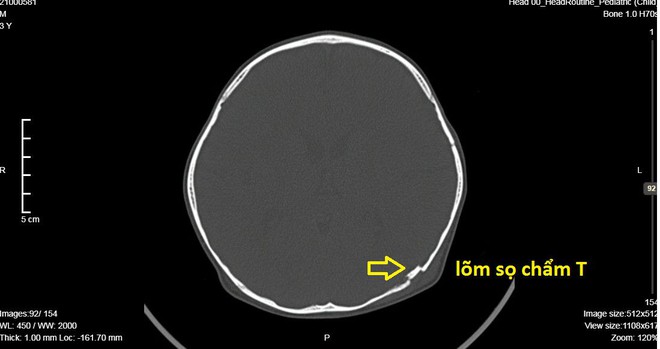

Qua thăm khám lâm sàng và kết quả chụp CT Scanner, ghi nhận bé B. bị lõm sọ não kín vùng chẩm trái (phía sau đầu). Một mảnh xương nhỏ lõm vào não cần phải được phẫu thuật khẩn cấp để nâng bản sọ lõm.